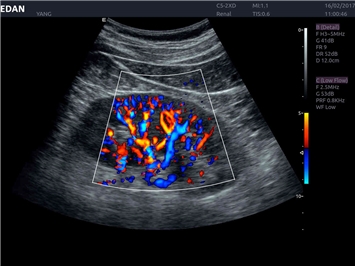

• Общей визуализации

Общая визуализация:

Да

Энергетический допплер: